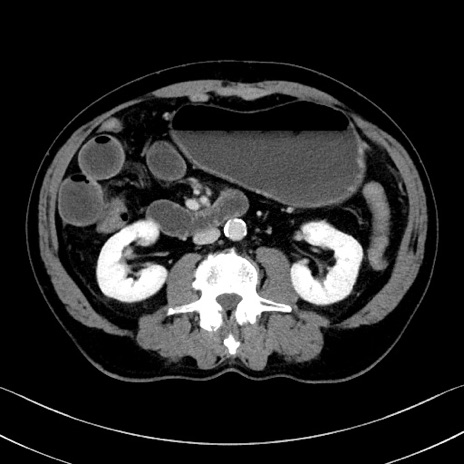

症例35(横断像)

【症例】70歳代 男性

【主訴】腹部膨満、嘔吐

【現病歴】昨日より腹部膨満感出現。本日増悪し、仙痛出現。嘔吐あり、受診。

【既往歴】糖尿病、胆摘後

【身体所見】BP 149/80mmHg、HR 74/min、BT 35.9℃、腹部:膨満、軟、圧痛なし。腸雑音減弱あり。上腹部正中切開瘢痕あり。

【データ】WBC 13500、CRP 1.72